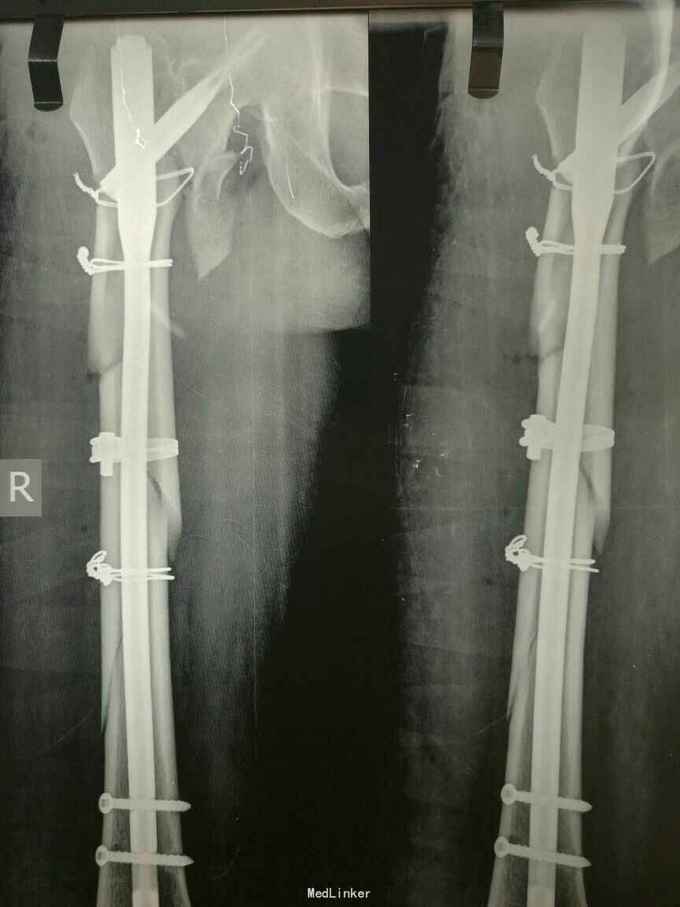

主诉:外伤后右大腿及右髋部疼痛,活动受限2小时 病史:患者自述于2小时前从高处摔伤右下肢及右手,伤后感右髋部右下肢及右手疼痛,活动受限,不能站起行走。自述未伤及头部。由家人送往我院诊治,经详细查体后以“右股骨骨折,右粗隆间骨折,右舟骨骨折”收入院。患者自入院以来精神状态尚可,未进食水,未排二便。

查体:右大腿皮肤无破损,大腿上段及右髋部软组织肿胀,未见皮下淤斑,右髋部及股骨近端环形压痛,局部可触及骨擦感及异常活动,右下肢纵向叩击痛阳性,肢端感觉良好,足背动脉可触及。右手近腕关节处肿胀,舟骨处压痛阳性,叩击痛阳性,右腕关节活动受限。 辅助检查:右髋及大腿x线示右股骨转子间粉碎骨折,对位对线尚可,右股骨干粉碎骨折,对位对线差,右手dr片右舟骨骨折,位置良好。

诊断:右股骨转子间骨折 右股骨干骨折 治疗:切开复位髓内钉固定术